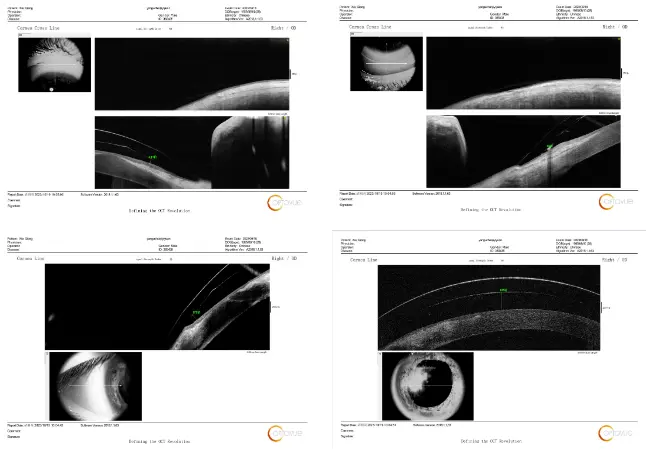

图:患者佩戴巩膜镜与角膜结膜间的距离